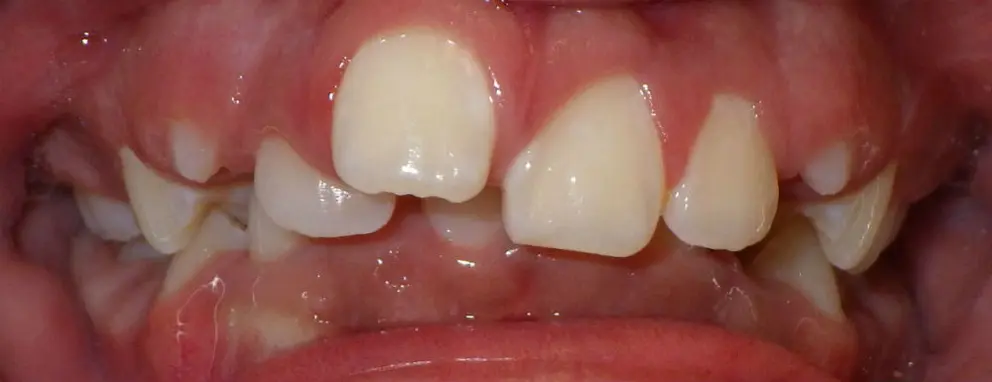

If you're not sure if your teeth are crowded – or if you’re concerned about your child’s teeth being crooked – there are a few signs you can look for to assess whether the teeth are crowded.

Signs of dental crowding:

- Crooked teeth set at unnatural angles in your mouth

- Teeth overlapping each other